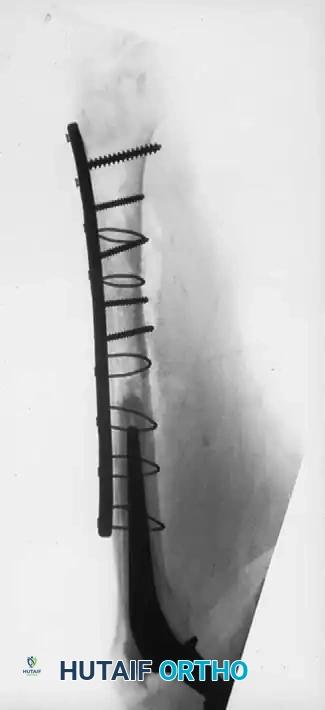

Associated Surgical & Radiographic Imaging